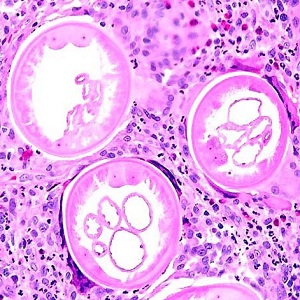

Several people developed gastrointestinal symptoms of watery diarrhea, nausea with vomiting, and low-grade fever approximately 1 week after attending a catered event. Stool specimens were collected for laboratory testing which included a formalin-ethyl acetate concentration with brightfield wet mount examination.